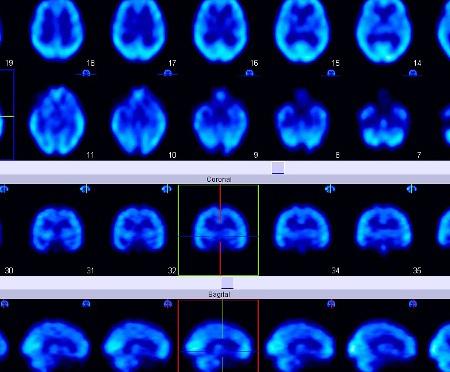

Parkinson’s disease (PD) is a neurological disorder that affects the motor functions of the brain and the production of dopamine needed to control body movements. It is a degenerative disease that causes movement problems, usually identified with the presence of tremors in the hands, slowness in pace, or rigidity in one’s posture. The impact of the disease differs from person to person, depending on how early the diagnosis was made, the patient’s symptoms, and response to medication. PD has been studied immensely and researchers have been able to conduct research in a multitude of fields pertaining to the subject, yet the exact cause of PD is still being studied. There are currently multiple advanced treatments for PD, but there is still no cure. Additionally, there are still no diagnostic tests that can directly identify PD, and diagnoses are instead being made based on patient medical history and physical exams (Armstrong & Okun, 2020).